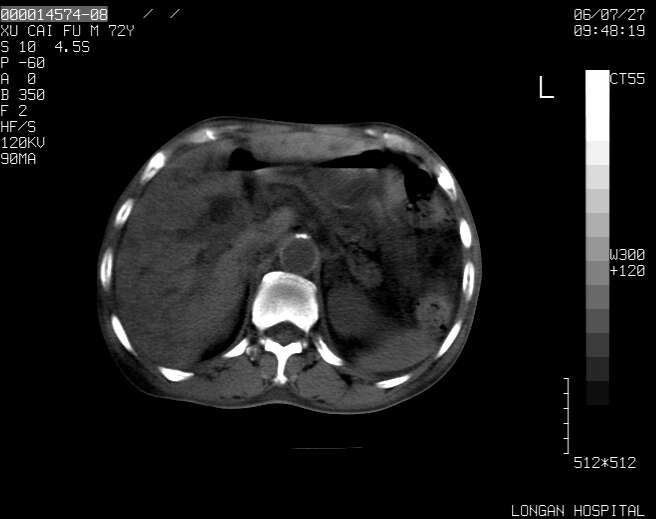

以下是引用winter在2006-7-30 20:14:00的发言:[br]1、考虑胆囊癌伴胆道侵犯并高位胆道梗阻、肝内多发转移、腹膜后淋巴结转移。[br]2、右肾轻度积水。[br]3、老人家72岁了胰腺头体尾部均较饱满,不过未见密度异常及其他异常征象。[br]4、腹水。

以下是引用jiajie在2006-7-31 7:10:00的发言:[br]考虑肝转移瘤,腹膜后淋巴结增大。[br]胃癌不能除外,建议胃镜检查。